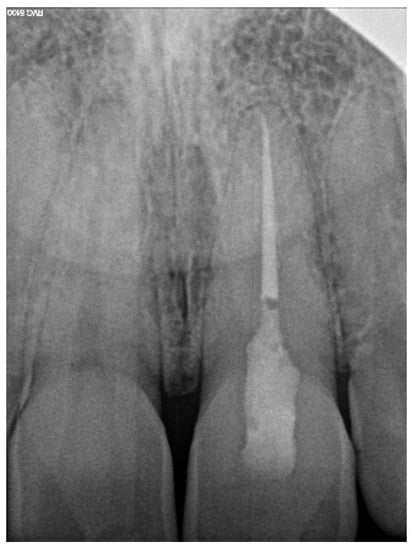

A 39-year-old male patient was referred to an endodontic specialist for the treatment of a maxillary left central incisor (tooth 21) before prosthetic treatment. Endodontic treatment had been initiated by the referring dentist, but as it was impossible for the clinicians to localize the root canal under the optical microscope, the treatment could not be completed, and the patient was referred to a specialist. The patient’s medical history revealed the absence of any systemic disorders or allergies. The dental history revealed trauma to the maxillary anterior region in childhood and subsequent gradual discolouration of the maxillary left central incisor. The patient presented with no complaints. Clinically, there were no pain or sensitivity to percussion or palpation. Tooth mobility was not increased. The tooth was restored by the referring dentist with a temporary restoration (composite resin) and showed no response to the pulp sensibility test (cold test). The radiograph and CBCT images showed that the endodontic treatment was initiated with wide access in the coronal part and confirmed root canal obliteration (Figure 16). After discussing the high probability of perforation and further tooth substance loss, an endodontic guide was designed.

Figure 16. The failed wide access in the coronal part and root canal obliteration on (a) X-ray and (b) CBCT images.

The correct fit of the guide was verified before and after the rubber dam was placed. The temporary filling was removed, and the previous access was checked with the guide, which revealed an almost correct path with no need to fill the created space. The Munce Discovery Bur #1, with a diameter of 0.8 mm (ISO head size 08), a length of 34 mm, and a speed of 10,000 rpm, was used through the guide for the first 2 mm. Due to the combined heights of the long coronal part and the guide sleeve, it was impossible to reach the demanded access with the bur. A 31-mm-long #10 K-file (VDW, Munich, Germany) was used through the guide to reach the desired length. The guide was removed every 2 mm to rinse the cavity and control the root path using the optical microscope. The canal was located at a length of 18 mm from the top of the guide sleeve—3 mm closer than the virtually planned depth. The working length was established using an electronic apex locator. A conventional root canal treatment followed (Figure 18). The time needed to localize the canal path in this case was approximately 10 min.

Figure 18. X-ray image showing the correctness of the performed root canal treatment.